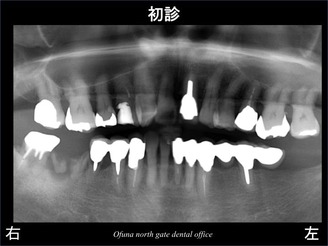

以下が初診時になります。

右下の奥歯の被せ物が取れたとのことで来院されました。

診査の結果、

虫歯が深く、

歯根破折 も起こしていました。

診断は抜歯です。

抜歯後は、インプラント治療を希望されました。

ここで問題となるのが 欠損した周囲の歯の状態です。